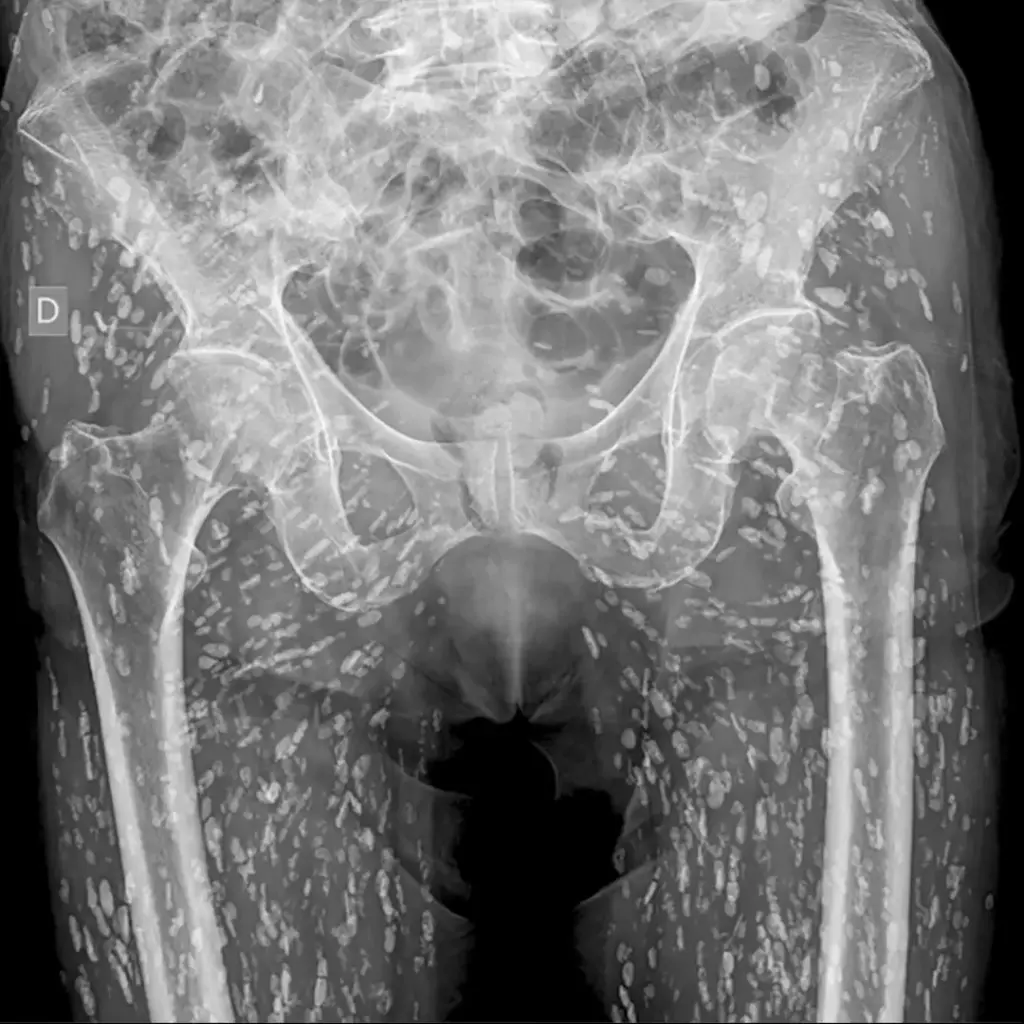

في ظل تداول صورة مُفزعة تُظهر وجود طفيليات في أنسجة أحد المرضى، نبّه طبيب إلى ضرورة توخي الحذر عند تناول لحم الخنزير، مُحذرًا بشكل خاص من تناوله نيئًا أو غير مطهو جيدًا، حيث يُمكن أن يُشكل خطرًا صحيًا كبيرًا نتيجة لوجود طفيليات ضارة، وذلك وفقًا لما نشر في موقع نيويورك بوست.

تُسمى هذه الحالة بداء الكيسات المذنبة، وهي عبارة عن عدوى طفيلية تُسببها يرقات دودة الشريط الوحيدة، وهي دودة شريطية تُصيب الخنازير بشكل أساسي، وتتطور هذه اليرقات داخل أنسجة الجسم المُصاب على شكل أكياس صغيرة، وتُسبب أعراضًا مختلفة حسب مكان وجودها في الجسم.